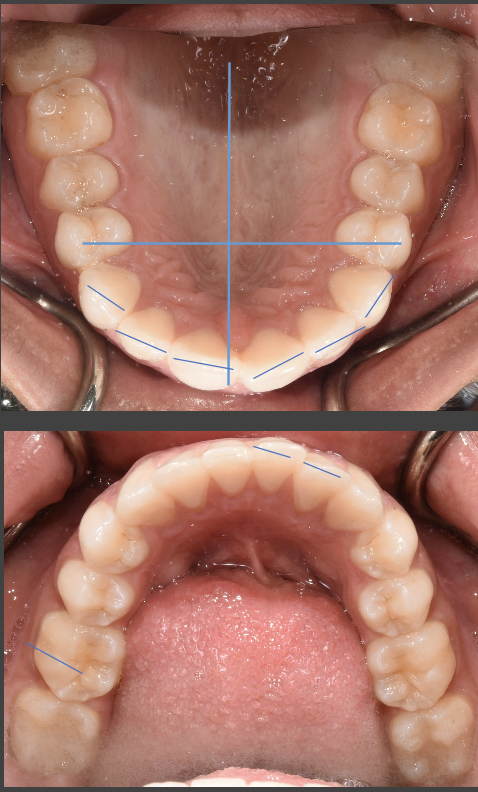

I have a baby lateral incisor that never fell out and my canine has fully grown in above my gum line, almost looking like it’s completely into of my gums. How would I go about fixing this bite? Are invisible aligners able to bring a tooth like this down and into place?

You are a great candidate for orthodontic treatment. From the picture, without seeing your molars or your natural occlusion, it is hard to see what bite classification you fall into. If your molars align properly, clear aligner therapy may be an option. However, if your natural bite is open, as pictured, traditional orthodontic treatment may be necessary. It is best to schedule a consultation with a dentist or orthodontist who provides both clear aligner therapy and traditional orthodontic options. He/she can best guide your decision based upon not only your current occlusion, but your treatment goals as well.